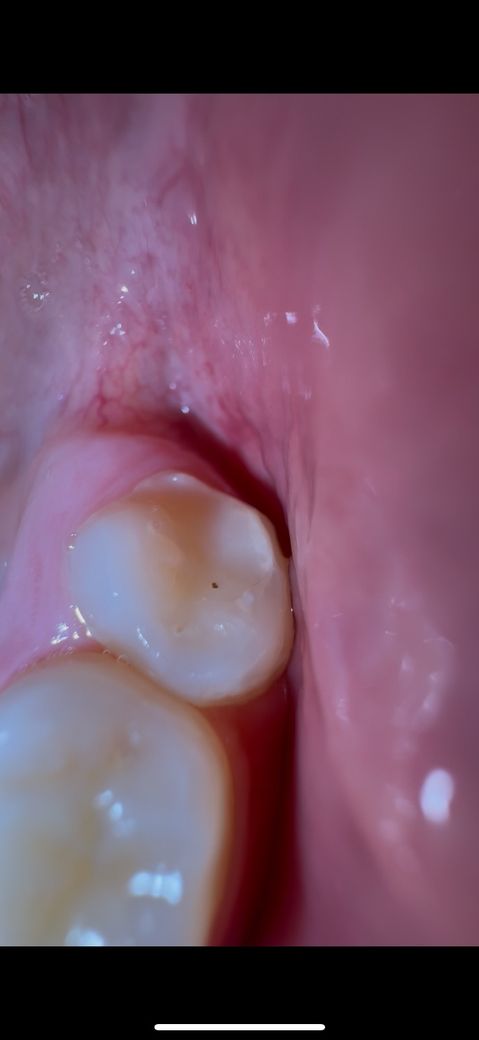

두번째는 아래이빨 오른쪽 맨뒤 어금니입니다 구멍이 난것 같아요

• 2번 째 사진

사진상에 보이는 충치는 심한 충치는 아니고 간단한 충치인거 같으니 치과에 가셔서 간단히 치료하시면될것같습니다.

2. 두번째 사진은 초기충치로 보여집니다